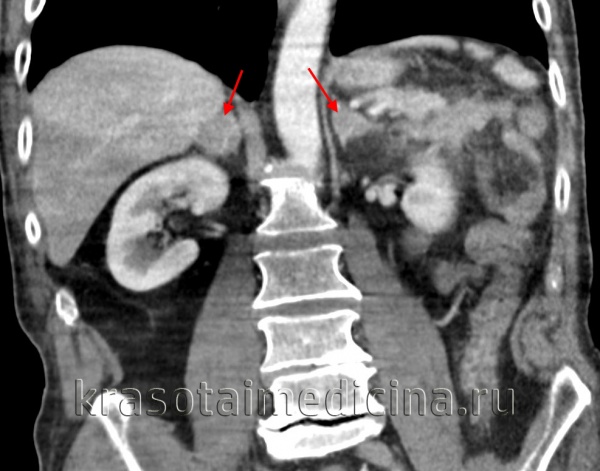

Патологическая анатомия феохромоцитомы. В 85—90% чаев феохромоцитома развивается в одном из надпочечников, причем одинаково часто как в левом, так и в правом. У 10—15% больных имеет место вненадпочечнико-вая локализация опухоли, которая может возникать в симпатических параганглиях по ходу брюшной аорты и у места ее бифуркации (наиболее частая локализация), в параганглиях грудной клетки. Описаны случаи локализации феохромоцитомы (параганглиомы) в полости черепа и стенке мочевого пузыря. У некоторых больных (10—12%) возникают множественные опухоли, располагающиеся в обоих надпочечниках или надпочечнике и параганглиях.

Феохромоцитома (хромаффинома) – доброкачественная или злокачественная гормонально-активная опухоль хромаффинных клеток симпатико-адреналовой системы, способная продуцировать пептиды и биогенные амины, включая норадреналин, адреналин, дофамин. В 90% наблюдений феохромоцитома развивается в мозговом слое надпочечников; у 8% пациентов локализуется в области аортального поясничного параганглия; в 2% случаев – в грудной или брюшной полости, в малом тазу; крайне редко (менее 0,1%) – в области головы и шеи.